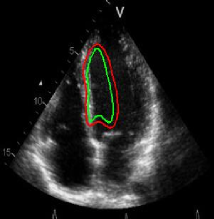

Refer to captionRefer to caption(a)(b)Refer to captionRefer to caption(c)(d)Refer to captionRefer to caption𝑎𝑏Refer to captionRefer to caption𝑐𝑑\begin{array}[]{cc}\includegraphics[width=112.0187pt,height=114.33119pt]{Ultra_init-1.pdf}&\includegraphics[width=112.0187pt,height=114.33119pt]{Ultra_Res-1.pdf}\\ (a)&(b)\\ \includegraphics[width=112.0187pt]{Ultra_init-2.pdf}&\includegraphics[width=112.0187pt]{Ultra_Res-2.pdf}\\ (c)&(d)\end{array}

Figure 13: Segmentation of endocardium in B-mode ultrasound images. (a) and (c) show the initializations provided, (b) and (d) show the converged contours. Image source: (a) was taken from [38] and (c) was taken from [39] .

In Figure 13, we show the results for segmentation of endocardium in B-mode ultrasound images, an imaging modality where shape prior information is popularly[40, 41] used to counter the problem of broken/diffuse boundaries between the region of interest and its background. In Figure 14, we show an example where the template based formulation is able to overcome partial loss of signal due to occlusion and still segment the object reliably. We observe that, by incorporating prior knowledge of the shape, we can segment images with partial loss of structure and broken boundaries.

We next develop templates for objects with hole(s) in their structure. These templates are called ring templates. Figures 15 and 16 show examples of ring templates. The area enclosed between the red contours act as region 1subscript1\Re_{1} and the area between the green contours is region 0subscript0\Re_{0}. Figure 17 shows the construction of the ring contours. The two seemingly unconnected contours are actually one connected contour. Hence, partial derivative calculations in equation (26) are still valid.

In Figure 15, the ring template has been used for segmenting the left ventricular (LV) wall of heart in cardiac MR images. Another example is shown in Figure 16. The template used in both examples has a greater thickness in the inner ring-shaped annular region than the outer annular region. This was done to facilitate obtaining the desired object’s structural information by means of the contrast (for example, between the endocardium and the LV wall) that a good initialization can offer. Hence, while designing a template, we can incorporate prior knowledge of the object and its surroundings.